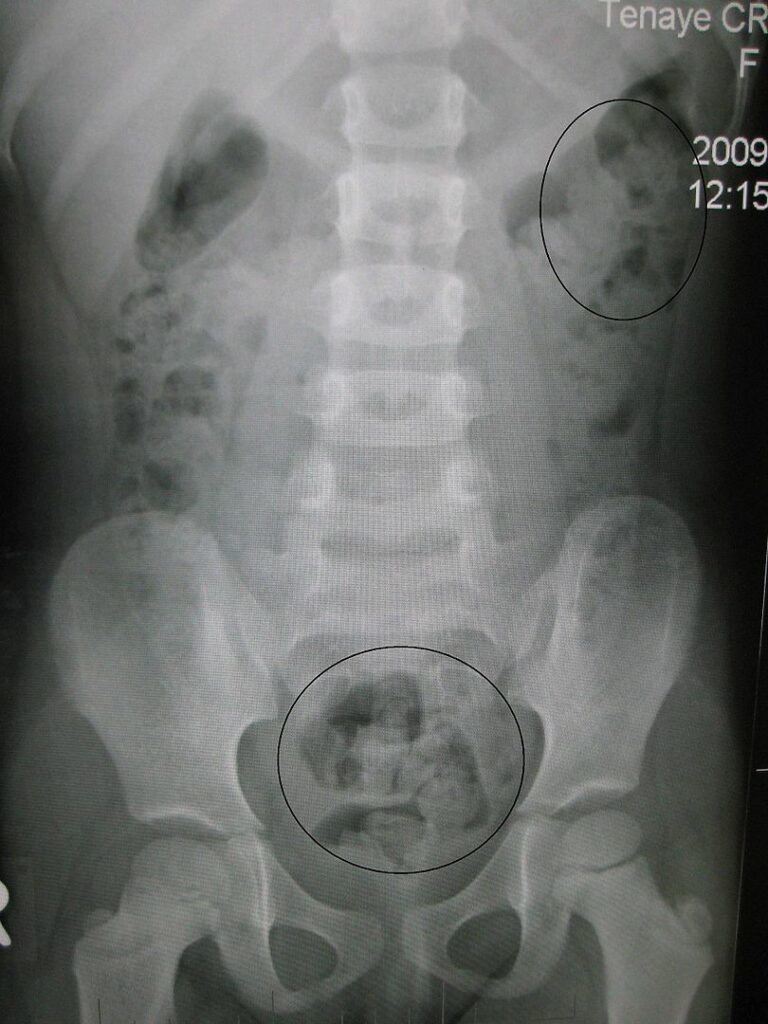

Pediatric Constipation Concise Medical Knowledge Constipated Baby Has Poop Stuck Keep reading for a lowdown on baby constipation symptoms, causes, treatment,. Painful passing of baby poop, also called stool. Symptoms of constipation in young children include: Hard stools can be difficult. If your constipated baby is at least a month old, you can give them a wee bit of 100% apple or pear juice. Hard stool that's either larger than. Constipated Baby Has Poop Stuck.